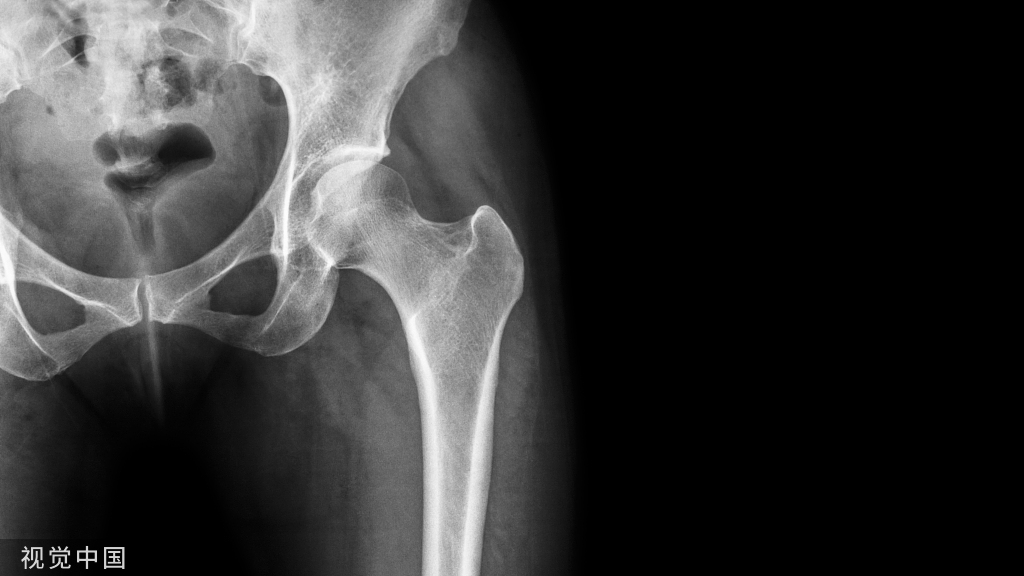

通过20世纪50年代ThomasWhitesides的一篇文章,FredL.Knowles获得了在棘突间植入金属来治疗腰椎疾病的启发。Wallis动态稳定系统于20世纪80年代早期开发,主要使用棘突间隙器联合棘突周围张力带来稳定腰椎。于2001年用于有症状腰椎退行性变,并且在保持腰椎活动度的同时增加硬度。第1代Wallis动态稳定系统由1个钛质棘间阻滞剂和涤纶人造韧带构成。目前的第2代由聚醚醚酮(PEEK)制成的棘突间阻断剂,以创造一种类似于椎体后部种植体的弹性模型。这种植入物的目的是卸载小关节突关节,减少应力,恢复椎间盘高度(dischigh,DH),保持腰椎术后活动性和稳定性。目前众多研究表明,该系统比单纯保守治疗具有明显临床效果。